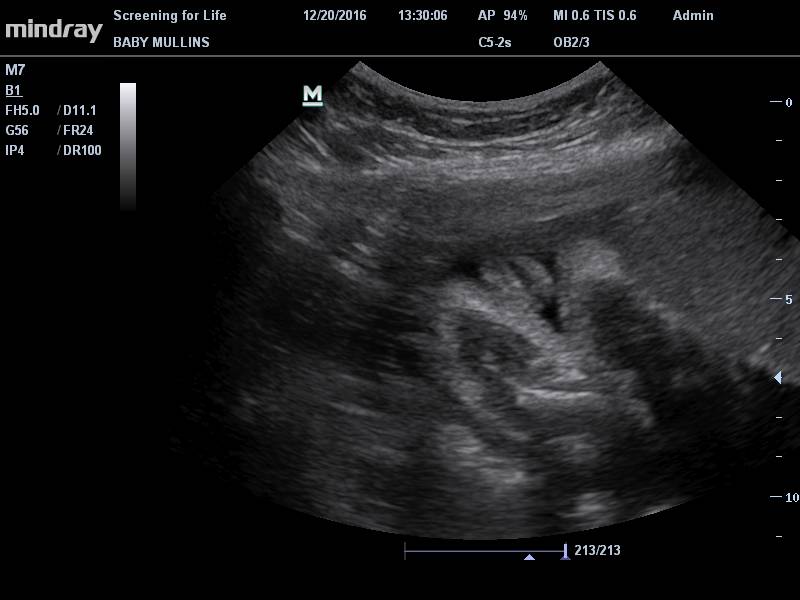

I know, I said we weren't going to find out, that we were ok with not knowing, blah blah blah. But....we (meaning I) felt like it was a good idea to have an actual sonogram to check everything else on the baby since there's already a VSD just to make sure everything else was ok. So on the 20th, we had an actual sonogram. I know, it wasn't even a week after the echo, but we did talk about it quite a bit, I sought opinions and advice from other people who I trust and it was almost all unanimously "go ahead and get a sonogram to double check everything else."

The baby is perfect (besides the VSD). At that appointment, the weight was estimated between 2.5 and 3.5 pounds, which is right on track. I had a baby check up immediately after and everything there was good, too. I'd gained 7 pounds and 5 cm in the previous 4 weeks because of a baby growth spurt (which explained all the aches and pains and feeling like I was practically exploding). I even got a birth kit to keep at home just in case the midwife doesn't make it to the birth and an updated birth list since we changed midwives. And I have everything on the list already, just a week later. I'm on top of this.

We debated being surprised at the birth on the gender, but Austin said "well, if they're checking everything else, might as well check that too so we can be ready." And I agreed. So....are you ready?

We're having another girl!

Chubby cheeks! I can't wait to squish them.

Again, the only time I will intentionally post pictures of my kids' genitals online.